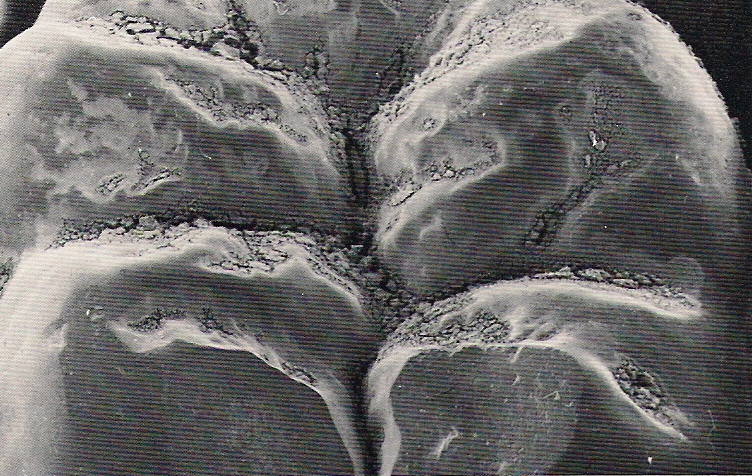

También otro de los temas que se trata con frecuencia, entrada a

estas edades, es la afección de la articulación temporo-mandibular,

(que es el principal elemento que ayuda a los movimientos de la

mandíbula). Debido al desgaste en la zona del disco del cartílago,

trae como consecuencia una limitación en el movimiento normal.